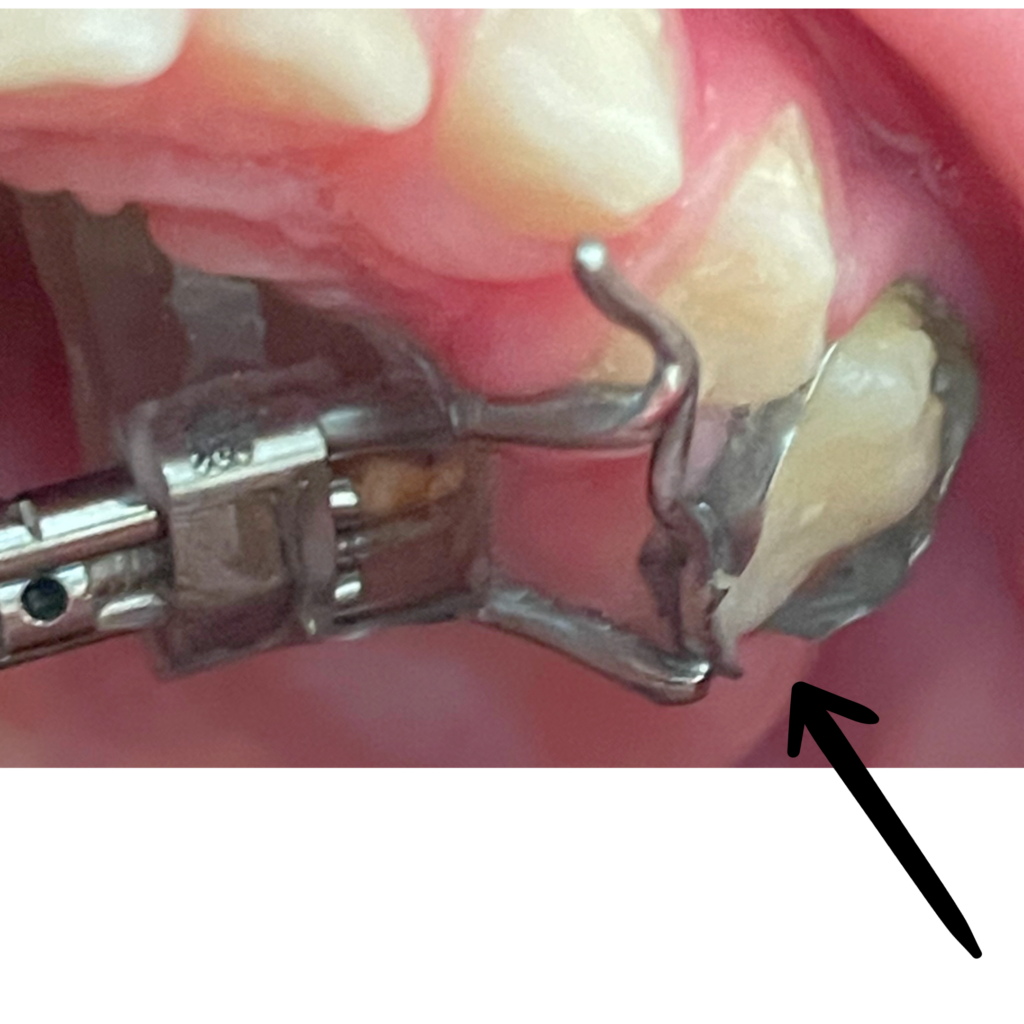

9. Microcargol afluixat, amb moviment o inflamació

En els tractaments amb aparells amb suport ossi, els cargols poden perdre força degut a restes de menjar que provoquen inflamació.

Si es dóna el cas, realitzeu els passos següents:

1. Contacteu amb la clínica Boca a Boca i agafeu hora amb la Dra. Villa. Els cargols són un tema quirúrgic i la Dra. Cubells no us pot ajudar en aquest sentit.

2. Higiene molt exhaustiva de la zona, especialment amb el fil dental i/o els raspallets interdentals. (Podeu mullar el fil o el raspallet amb clorhexidina).* Instruccions d’higiene

3. Apliqueu Gel de clorhexidina la llaga, després de cada raspallat i a demanda entre raspallats si cal.* (Producte complementari a les instruccions d’higiene; ells sols NO solucionaran la inflamació).

Microcargol anclat

Microcargol afluixat